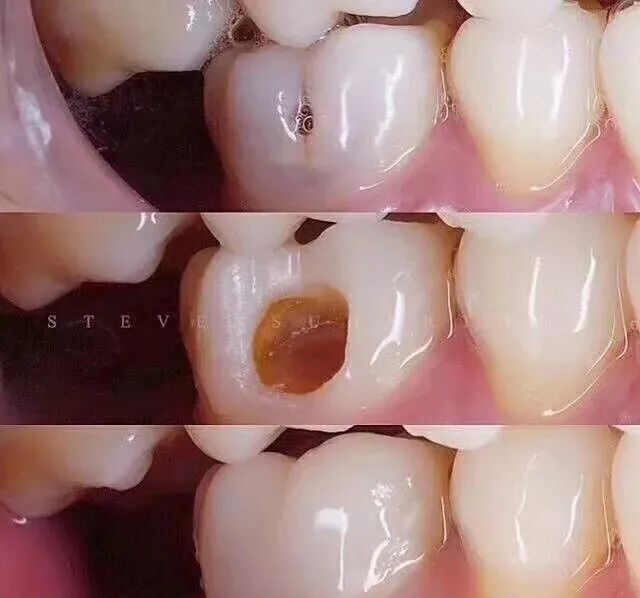

第一階段:牙齒咬合面有黑線,大牙一般最常見,說明開始蛀牙了,牙釉質被細菌齲壞,但不痛不癢,會出現窩溝齲得及時補牙,而不是去洗牙;

第二階段:牙齒出現小黑洞,說明引起中度蛀牙,細菌腐蝕來到牙本質,伴隨著牙齒敏感,黑色腐敗物質其實就是細菌的産物,這時候還可以再補牙;

第三階段:牙齒超過一半爛掉,說明已經重度蛀牙,細菌傷及牙髓牙神經,還伴隨著劇烈疼痛,牙神經病變這時得根管治療處理,挽救傷痕累累的牙齒。